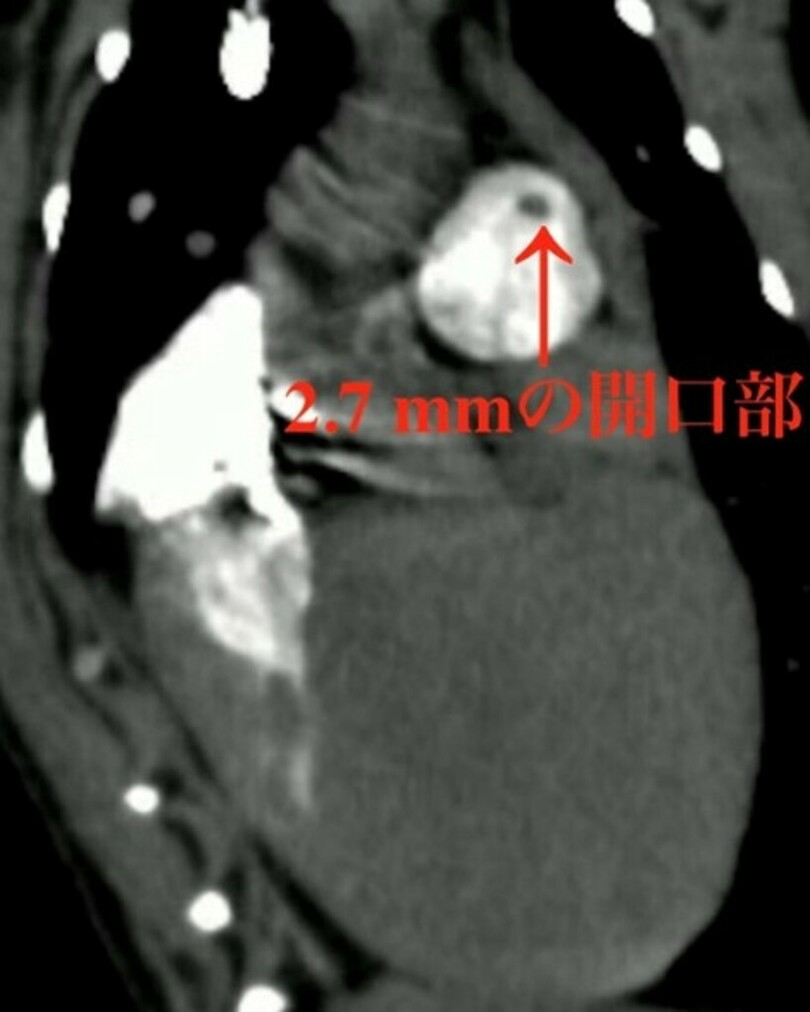

そこで我々は、この問題を解決するためにContinuous HIgh-Enhanced COntrast (CHIECO)法と名付けた特殊な心電同期CT造影検査法を開発し、直径2.7 mmの僅かな開口部を明瞭に描出することに成功しました。またそれだけでなく、非侵襲的に3次元的な血液の流れを可視化することも可能となりました。